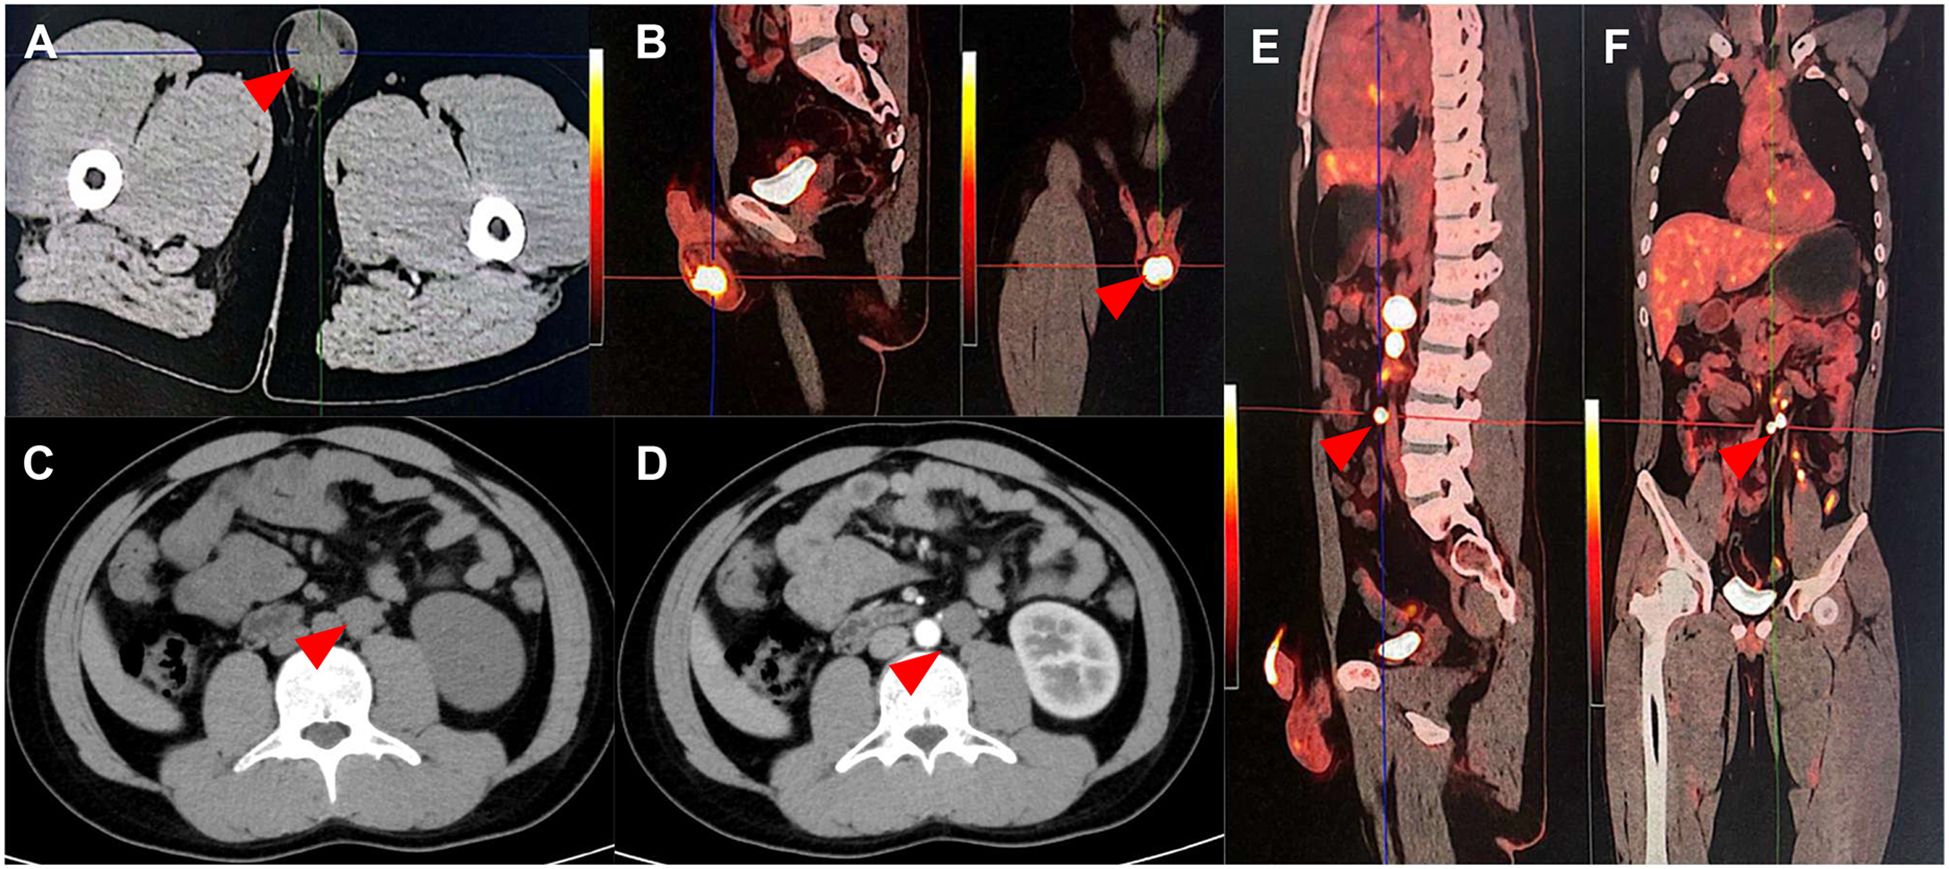

Abstract Background: Zinner syndrome is a rare congenital disorder of the urogenital system. In current reports, cases of Zinner syndrome complicated by malignant tumors are even rarer. Case Description: We reported a 26-year-old male with Zinner syndrome complicated by testicular embryonal carcinoma and retroperitoneal lymph node metastasis. He received orchiectomy, chemotherapy and a retroperitoneal lymph node dissection with favorable response. Conclusions: As suggested by this rare case, Zinner syndrome may be bound up with genitourinary malignancy tumor. When diagnosing congenital disorders of the urinary system, it is essential for clinicians to take into consideration potential complications. More importantly, it is also paramount to account for the similarities and differences in diagnosis and treatment between comorbid and isolated conditions.